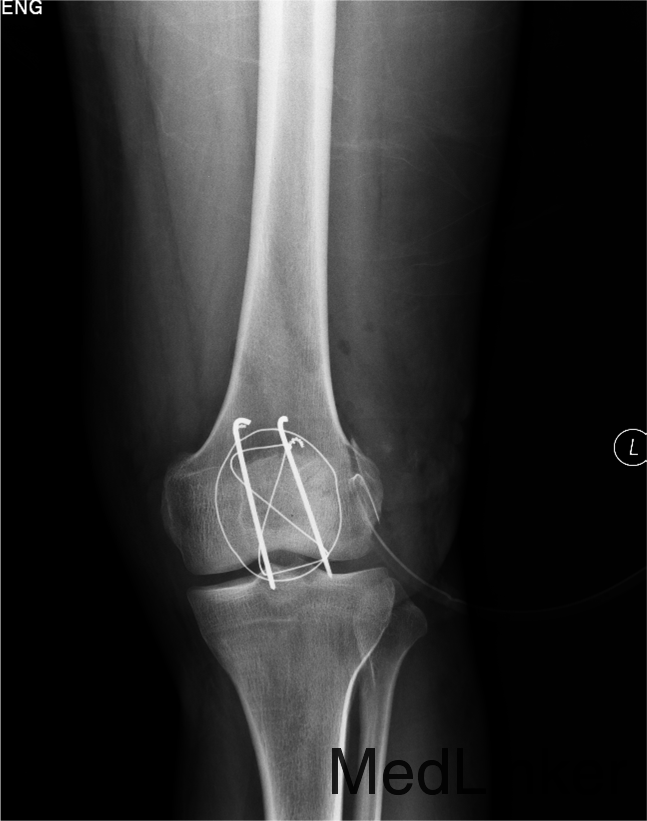

患者自述于2014年4月24日11点左右自马车坠落,摔伤致左膝关节疼痛、流血、活动受限,患者于当地医院行左膝X线检查,提示:左髌骨骨折,包扎,为进一步处理。患者现无意识障碍,无视物不清,无头晕、头痛,无恶心、呕吐,无胸闷及呼吸困难,无腹胀、腹痛。现平素饮食睡眠良好,二便如常。发病近期体重无明显下降。

左膝见一长约10cm的开放口,压痛(+)。未触及骨擦感及异常活动,未闻及骨擦音,患肢无明显 麻木,左下肢血运良好,余肢体查体未见明显异常。

患者入院后急诊行左髌骨清创缝合术,左髌骨骨折切开复位张力带内固定术。术后局部换药无红肿渗出,冷敷,甘露醇消肿,患肢抬高。患者术后14无不良主诉给予拆线。